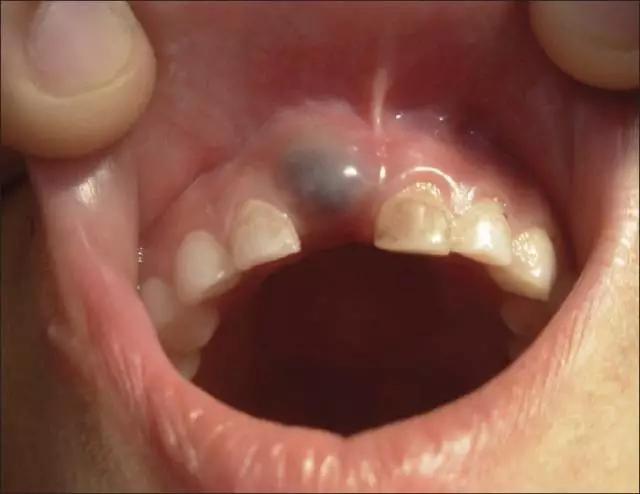

在孩子长牙的时候,口腔中前牙区域或后牙区域,有可能出现一种“蓝色或灰色的血肿”,这就是“萌牙血肿”或"萌牙囊肿"。(如下图)

呈球状肿胀的蓝色萌牙血肿

萌牙位置出现了肿胀,当触摸的时候会感到湿湿软软的,并且有液体充斥在肿胀里面。这就称为"萌牙囊肿"。